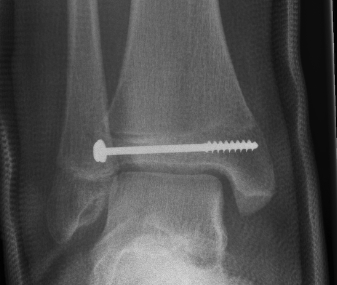

Salter Harris III / Tillaux

Definition

- SHIII of anterolateral distal tibia

- epiphyseal avulsion of AITFL

- supination / ER injury

Management

ORIF

- reduce articular step / prevent physeal bar

- anterolateral incision to reduce

- either anterolateral 4 mm cannulated screw or

- place screw percutaneously from medial side